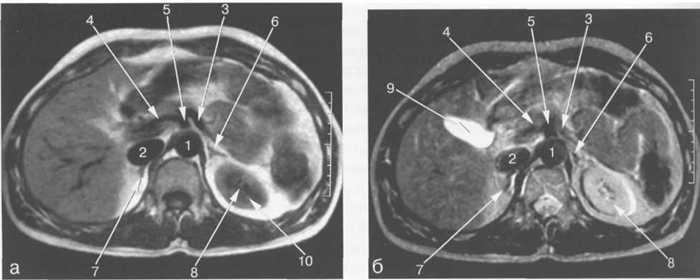

Рис. 9.47. МРТ сердца. Аксиальная плоскость.

Здесь и на рис. 9.48—9.52:

I — правый желудочек, 2 — левый желудочек, 3 — правое предсердие, 4 — левое предсердие, 5 — межжелудочковая перегородка, 6 — межпредсердная перегородка, 7 — задняя стенка левого желудочка, 8 — восходящая часть аорты, 9 — дуга аорты, 10 — нисходящая часть аорты, 11 — легочный ствол, 12 — правая легочная артерия. 13 — левая легочная артерия, 14 — верхняя полая вена, 15 — нижняя полая вена, 16 — трахея.

На рис. 9.47—9.52 представлены Т1-ВИ наиболее часто используемых МР-сечений сердца.

Рис. 11.24. MPT брюшной полости в аксиальной плоскости на уровне надпочечников.

а-Т1-ВИ;б-Т2-ВИ.

1 — аорта; 2 — нижняя полая вена; 3 — селезеночная артерия; 4 — общая печеночная артерия; 5 — чревный ствол; 6 — левый надпочечник; 7 — правый надпочечник; 8 — левая почка; 9 — желчный пузырь; 10 — Бертиниевы столбы левой почки.

Сосуды ворот селезенки хорошо видны во всех импульсных последовательностях (рис. 11.24). Селезеночная вена определяется как структура продолговатой формы, которая зачастую имеет горизонтальное расположение (см. рис. 11.12). Селезеночная вена используется в качестве ориентира для локализации хвоста и тела поджелудочной железы, которые располагаются кпереди от нее (см. рис. 11.12, 11.14). В области ворот внутриселезеночные сосуды видны как разветвляющиеся продолговатые структуры.